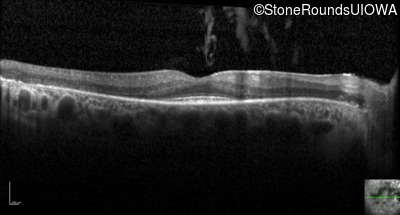

Optical Coherence Tomography - Right - 20/32

Exemplar / OCT Stack

OCT Stack